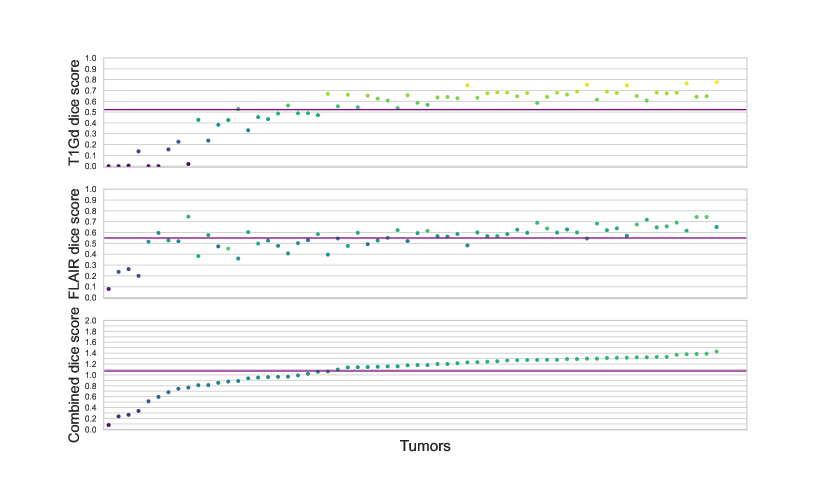

Tab.2 showcases how the difference between real and synthetic data distributions affects the query accuracy. Given there is an evident gap between real tumor progression and the tumor growth trajectory modeled by the reaction-diffusion model, we expectedly observe ca. 10 percent drop of the accuracy. Fig. 2 and 3 demonstrate the same difference in real and synthetic data distributions for every example used in the study. In a way, in future works probing more complicated tumor descriptions, such analysis can serve as a measure of plausibility of a tumor growth model.